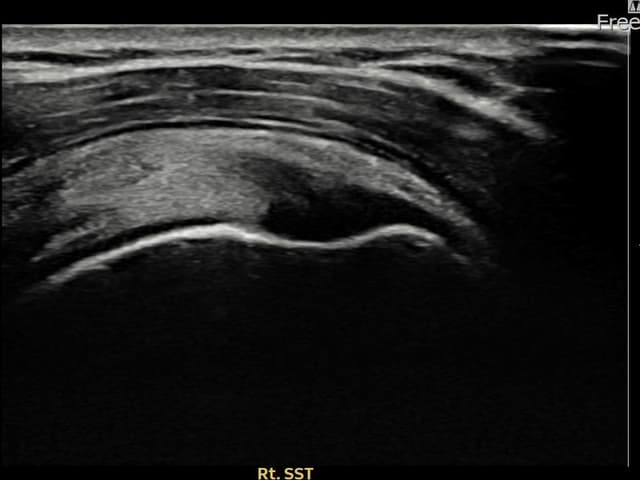

[촬영시기:22.09.19~22.12.09]

[어깨인대 축소봉합술] 우측 어깨 통증과 팔을 특정 각도로 올릴 때 심해지는 충돌 증상으로 내원하셨습니다.